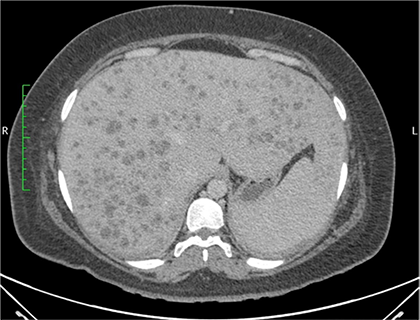

Dentro la evolución del cuadro clínico la paciente presentó una evolución estacionaria, persistiendo con taquicardia, y taquipnea, además de leucocitosis de 19 200 con neutrofolia de 95%, a pesar de haber removido la causa de la obstrucción (coledocolitiasis) y haberse administrado antibióticos (ceftriaxona 1 g EV cada 12 horas y metronidazol 500 mg EV cada 8 horas) durante 72 horas. Es así, que se realiza nueva ecografía abdominal (Figura 2) la cual reportó: “microabscesos hepaticos?, dilatación de vía biliar extrahepática hasta 18 mm y vesícula con barro biliar”, por lo que tras ser valorada por el servicio de medicina interna se decide realizar tomografía axial computarizada (TAC) de abdomen con contraste y en el contexto de una sepsis de foco abdominal por probables microabscesos hepáticos se decide rotar el esquema de tratamiento antibiótico a meropenem 1 g EV cada 8 horas, descontinuando ceftriaxona, y continuando metronidazol 500 mg EV cada 8 horas. En misma fecha se realiza TAC de abdomen con contraste (Figura 3 y 4) la cual reporta: “hepatomegalia, innumerables microabscesos hepáticos, dilatación de vía biliar intra y extrahepatica, a descartar engrosamiento de la pared lateral izquierda de la vesícula biliar, ganglios periportales de etiología por determinar (origen inflamatorio vs metastásico) y mínimo derrame pleural bilateral”. Posteriormente, se solicitan marcadores tumorales de CA 19.9, CA 125, AFP y CEA, todos ellos con resultados dentro de parámetros normales.